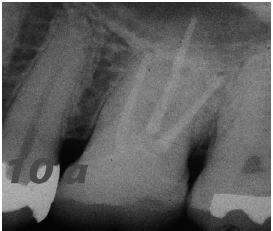

Radiografía final del tratamiento endodóntico

Control radiográfico a los 18 años